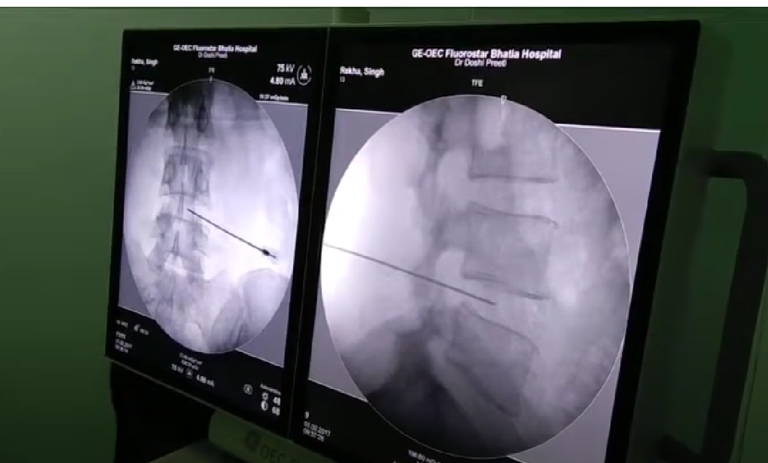

تزریق ترانس فورامینال (Transforaminal Injection) یکی از روشهای درمانی است که برای کاهش دردهای ناشی از مشکلات ستون فقرات، به ویژه مشکلات عصبی مانند دردهای